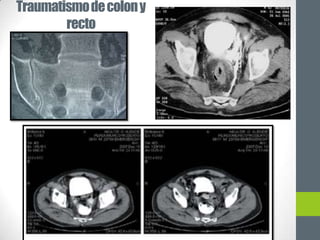

Traumatismo de colon y

recto

Engrosamiento y

contusión de la pared

intestinal, gas intra

o retroperitoneal o

extravasación de

liquido o contraste

TRAUMATISMO RENAL